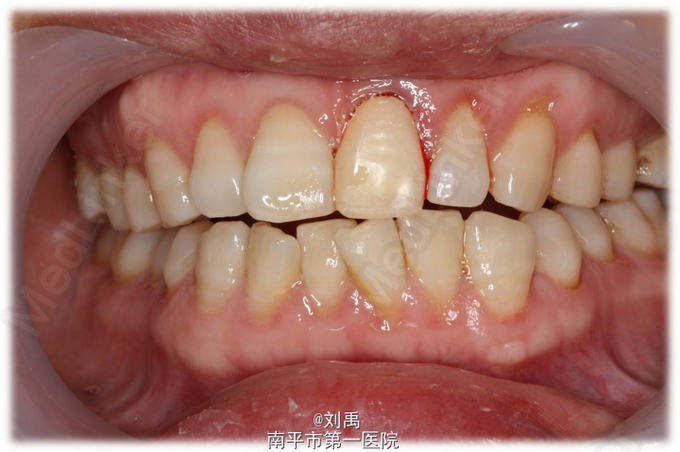

诊断:残冠 切龈后,预备桩道,植入纤维桩,牙体预备,比色,戴暂冠,复诊戴牙

残冠位于龈下或牙龈组织增生使两侧牙龈不对称时,在牙体修复时可先考虑切龈,这样不仅备牙时更容易,也有利于修复体边缘的密合,更有利于美观。